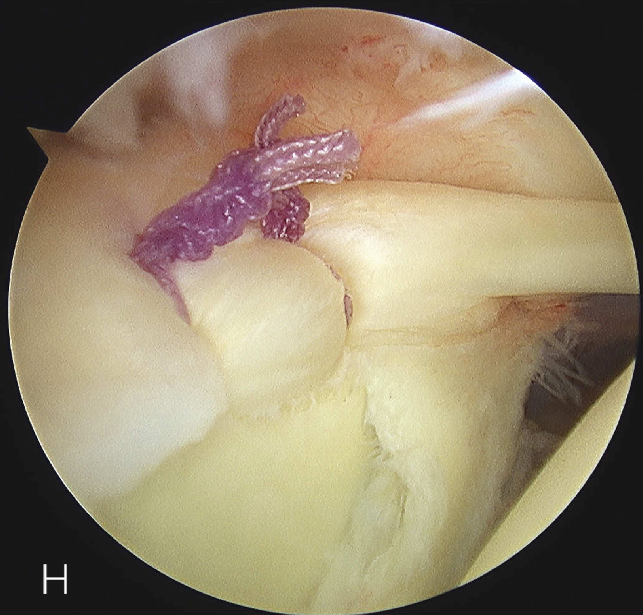

上盂唇修复

创建前方和后方入路时,与关节盂面成恰当角度,以便锚钉的置入。 高位和外侧放置前方入路可以有效地进行单纯上盂唇的修复。该入路位于肩袖间隙的高位和外侧,用腰椎穿刺针进行定位。非刚性套管有助于在肱二头肌腱附着部后方置入锚钉。 可用于 SLAP 修复的辅助入路包括 Wilmington 入路(肩峰后外侧角前方、外侧各 1 cm 处)或 Neviaser 入路(锁骨、肩峰、肩胛冈组成的三角形内,肩峰内侧 1 cm 处)。

修复处准备

肩袖部分撕裂的修复